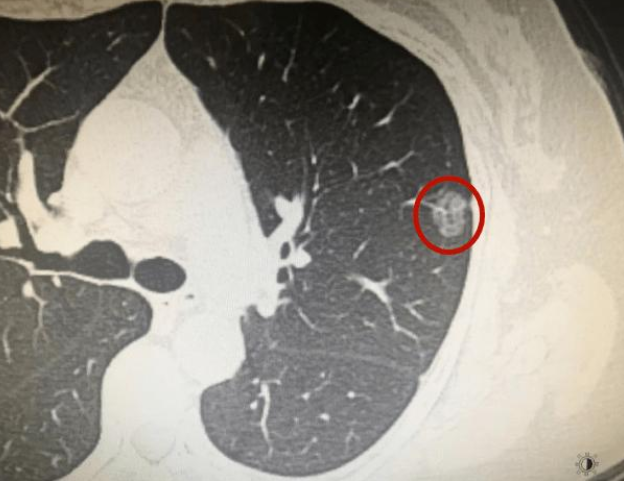

结节在医学不同专业、不同部位的解释都不一样,这里我们以肺结节为例,结节指的是边界清楚、影像不透明、直径小于或等于 3mm、周围为含气肺组织所包绕的病变。通常可分为实性与非实性结节。发现结节不等于就有恶性肿瘤存在,还需进一步鉴别诊断按是否有恶性肿瘤、良性病变、感染病变以及非感染性病变等。直径小于4 mm 的孤立微小结节是原发性肺癌的机率小于1%,反之,直径为8 mm 的小结节是原发性肺癌的机率则上升10%~20%。毛玻璃样密度定义为: 在高分辨力 CT 上呈模糊的致密影而其中仍能见到支气管结构或肺血管,毛玻璃密度影的原因比较多,例如炎性病变,肺泡出血以及肿瘤性病变。按影像学表现分为纯毛玻璃密度影和混合毛玻璃密度影,在早年的一些文献报道中,单纯毛玻璃结节中肺癌患病率为18%,混合毛玻璃结节中肺癌患病率为63%,因此混合毛玻璃结节需要更加积极处理。临床上指的是病理性钙化,除骨和牙齿外,在机体的其他组织发生钙盐沉着的现象,一是代谢后的产物、 二是感染与发炎后的痕迹、 三是肿瘤发展过程中因坏死及炎性反应而形成的组织变化。